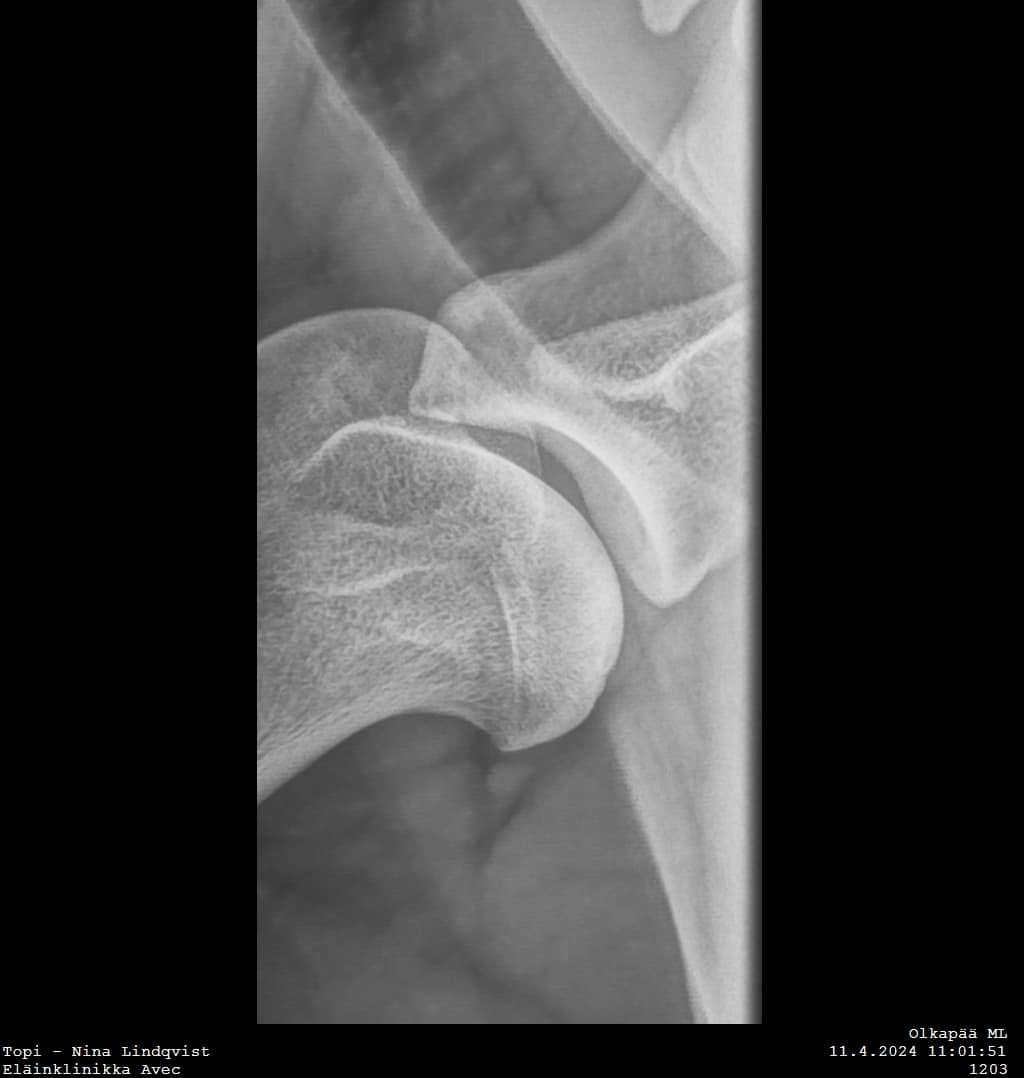

Topi was operated on Tuesday at Eläinklinikka Morelius by DVM Mikael Morelius. Both shoulders were operated by arthroscopy. On the left side there was a appr. 10 mm wide piece of cartilage removed. On the right side, which is also affected, the situation was calm and nothing was done. Everything went well!